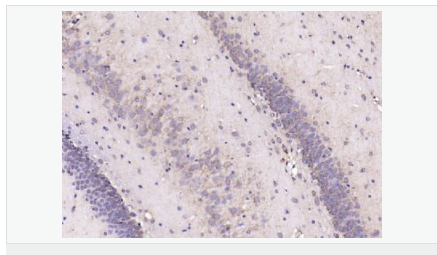

| 產(chǎn)品應(yīng)用 | ELISA=1:5000-10000 IHC-P=1:100-500 IHC-F=1:100-500 IF=1:200-800 (石蠟切片需做抗原修復(fù)) not yet tested in other applications. optimal dilutions/concentrations should be determined by the end user. |

| 產(chǎn)品介紹 | This gene encodes a member of the corticotropin-releasing factor family. The encoded preproprotein is proteolytically processed to generate the mature neuropeptide hormone. In response to stress, this hormone is secreted by the paraventricular nucleus (PVN) of the hypothalamus, binds to corticotropin releasing hormone receptors and stimulates the release of adrenocorticotropic hormone from the pituitary gland. Marked reduction in this protein has been observed in association with Alzheimer's disease. Autosomal recessive hypothalamic corticotropin deficiency has multiple and potentially fatal metabolic consequences including hypoglycemia and hepatitis. In addition to production in the hypothalamus, this protein is also synthesized in peripheral tissues, such as T lymphocytes, and is highly expressed in the placenta. In the placenta it is a marker that determines the length of gestation and the timing of parturition and delivery. A rapid increase in circulating levels of the hormone occurs at the onset of parturition, suggesting that, in addition to its metabolic functions, this protein may act as a trigger for parturition. [provided by RefSeq, Nov 2015] Function: This hormone from hypothalamus regulates the release of corticotropin from pituitary gland. Subunit: Interacts (via C-terminus) with CRFR1 (via N-terminal extracellular domain). Subcellular Location: Secreted. Similarity: Belongs to the sauvagine/corticotropin-releasing factor/urotensin I family. SWISS: P06850 Gene ID: 1392 Database links: Entrez Gene: 1392 Human Entrez Gene: 12918 Mouse Omim: 122560 Human SwissProt: P06850 Human SwissProt: Q8CIT0 Mouse Unigene: 75294 Human Unigene: 290689 Mouse Unigene: 10349 Rat Important Note: This product as supplied is intended for research use only, not for use in human, therapeutic or diagnostic applications. CRF陽性神經(jīng)元的胞體廣泛分布于下丘腦的室旁核、背縫核和藍(lán)斑核,這些區(qū)域也是去甲腎上腺素(NE)神經(jīng)元與5-羥色胺(5-HT)神經(jīng)元密集的區(qū)域。 CRF既具有神經(jīng)遞質(zhì)的性質(zhì)又具有神經(jīng)激素的性質(zhì)。CRF是聯(lián)系神經(jīng)系統(tǒng)與內(nèi)分泌系統(tǒng)的橋梁,在情感障礙疾患如焦慮和抑郁的發(fā)病中發(fā)揮重要作用. |